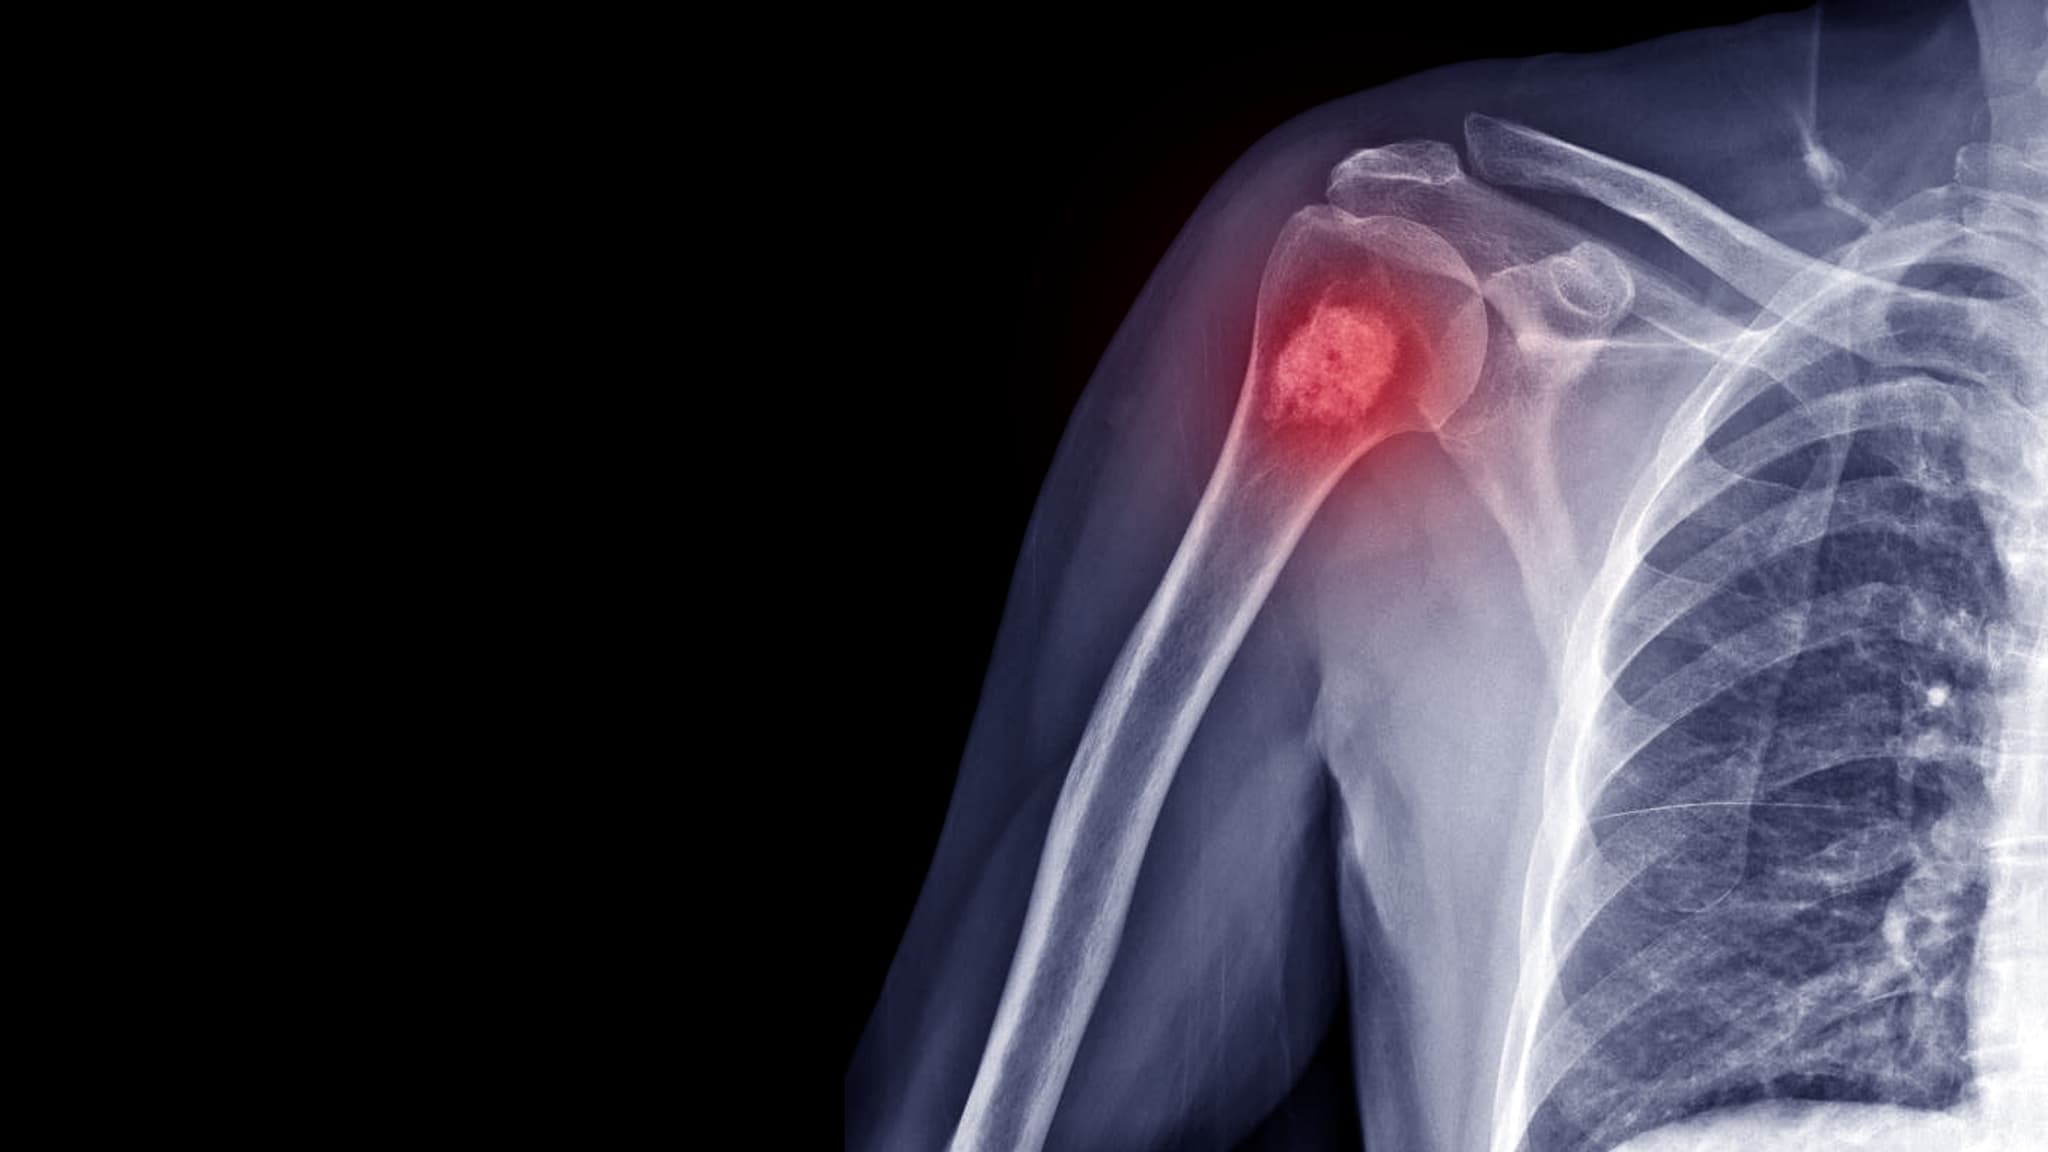

Bone cancer is a rare but serious form of cancer that begins in the bones. It occurs when abnormal cells grow uncontrollably in the bone tissue. Bone cancer can either originate in the bones (primary) or spread from other parts of the body (secondary/metastatic). Common types include osteosarcoma, Ewing sarcoma, and chondrosarcoma.

Osteosarcoma is the most common type of bone cancer, often affecting children and young adults. It usually begins in the long bones like the arms and legs.

Bone cancer diagnosis may involve the following steps:

Bone cancer symptoms often overlap with common orthopedic conditions. Recognizing persistent pain, swelling, or fractures that don’t heal is vital. Early detection leads to more treatment options and better outcomes.